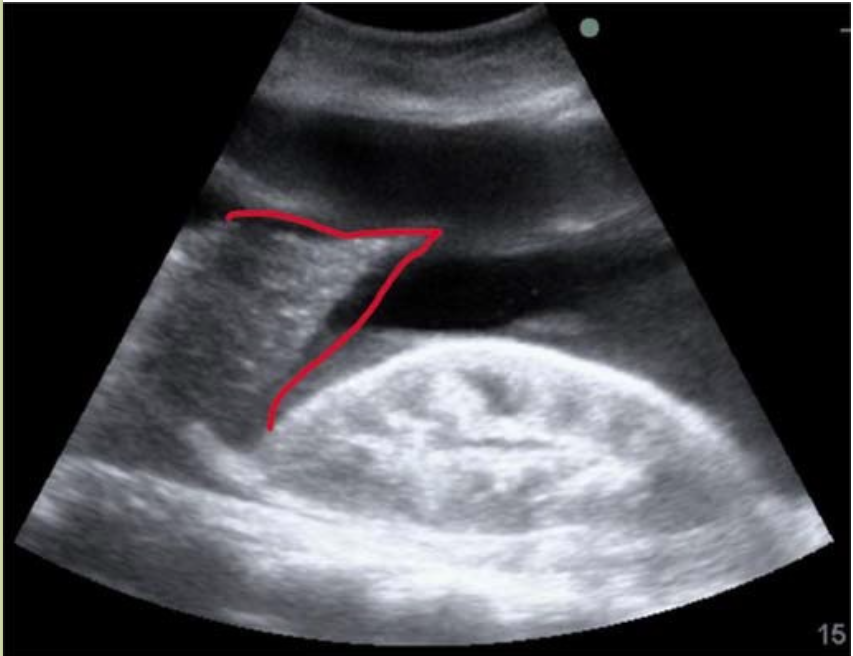

肺实变

肺炎、肺不张、肺肿瘤等均可出现肺实变,超声可表现为实质性回声区,貌似肝脏组织,如能显示到膈肌,则易与肝脾相区别。